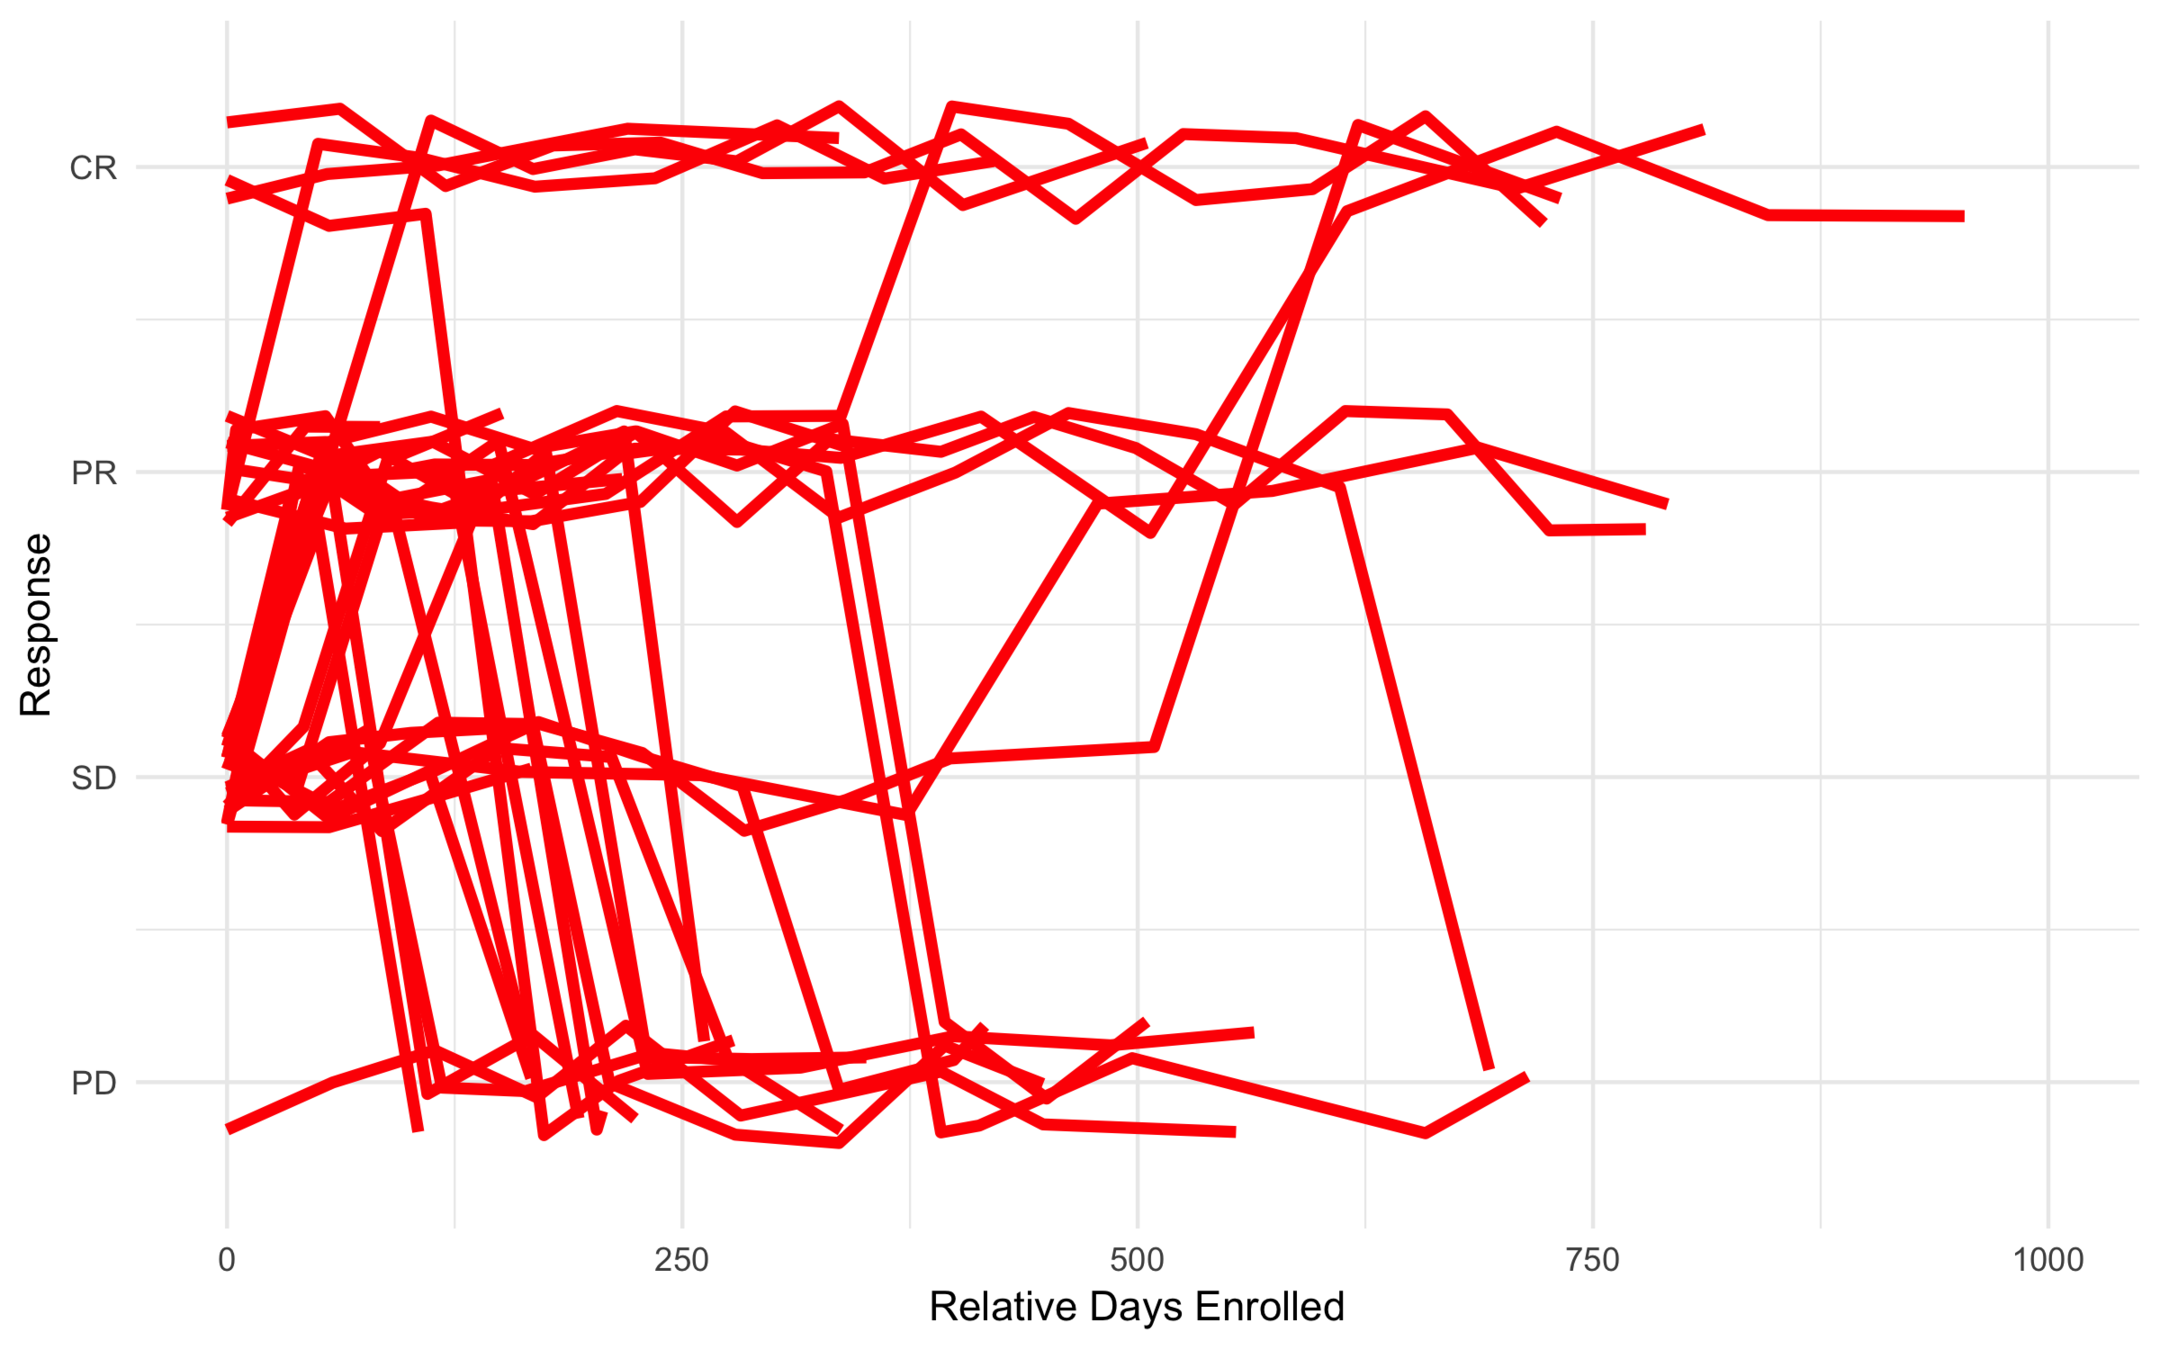

All Trajectories

Low Risk

Intermediate Risk

High Risk

Anonymous Drug 1

Was found to be effective for a certain type of cancer.

Ran into problems with severe toxicity events (449 toxicities out of 607).

Goal was to find subtypes least (or most) likely to have toxicity events.